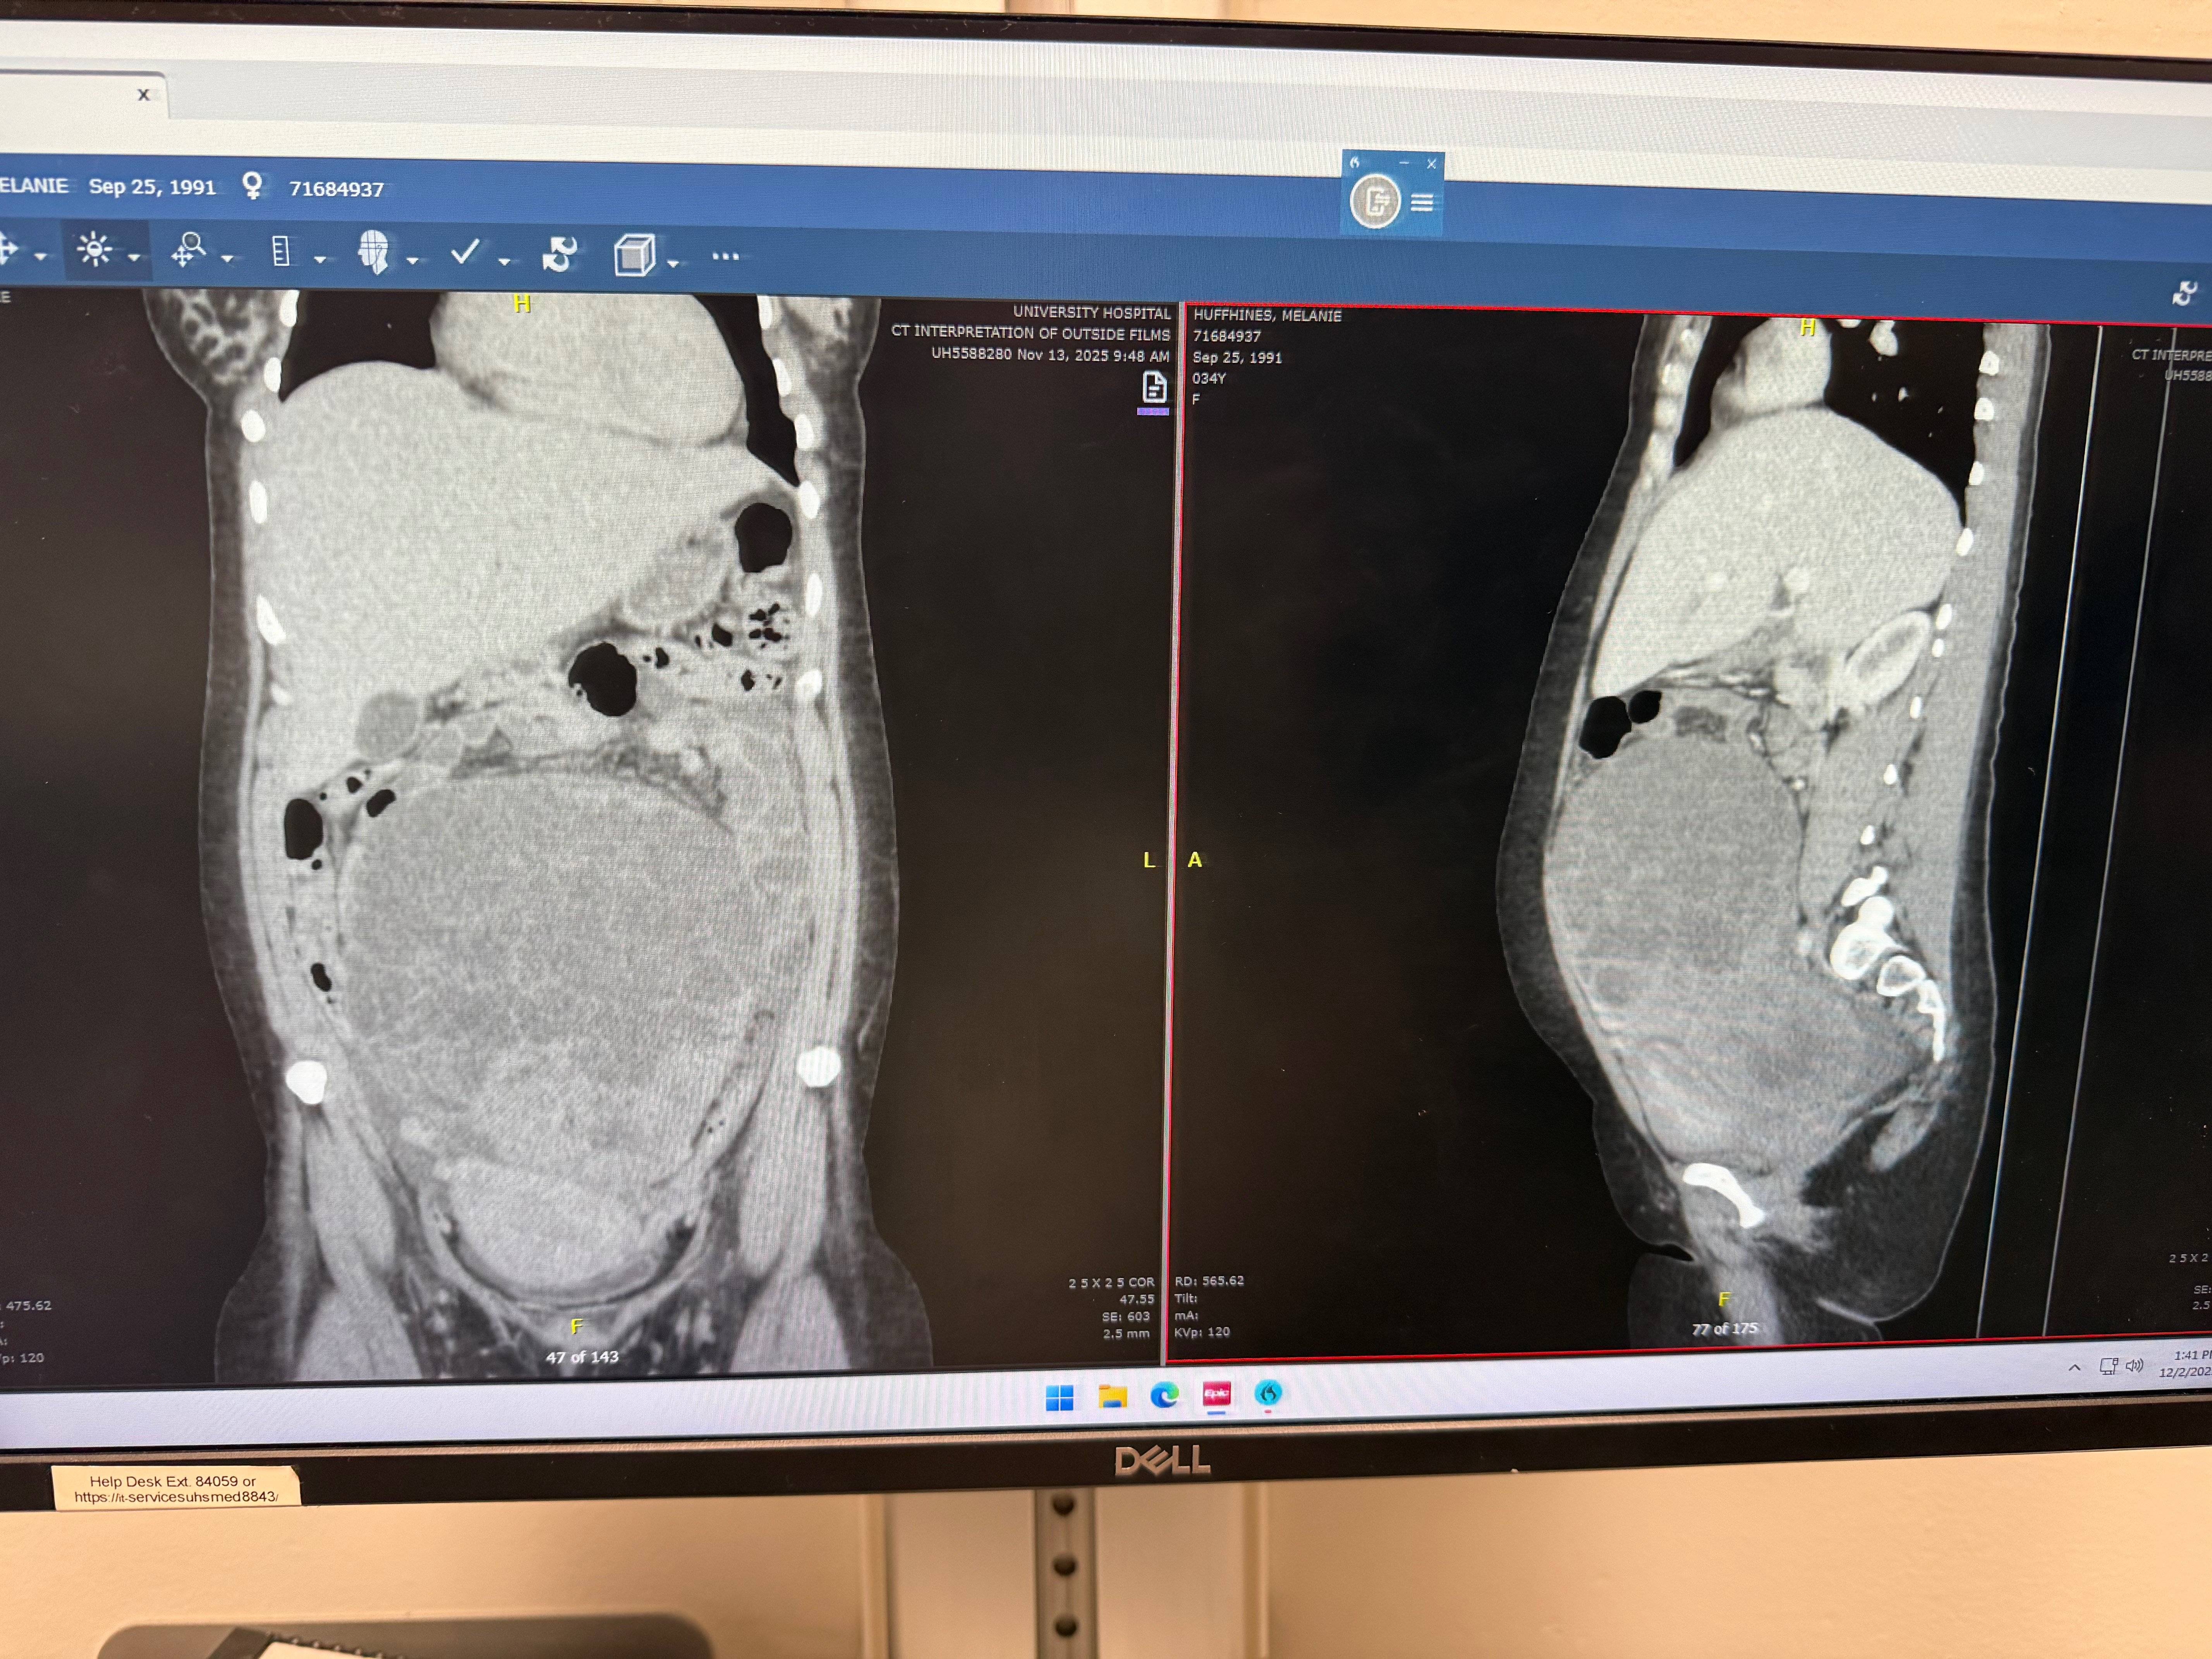

I’ve never made one of these before but at this point it is a necessity. Our happy little world just got absolutely rocked this past week. We just got married this September. About a month later I started having what really seemed like a bad gastritis flare ups. The pain got so bad that I ended up going to the ER here in corpus on Thursday, where they did an CT scan, which showed what was not gastritis but a large mass covering nearly my entire abdomen. They immediately told me I needed to go to San Antonio to the oncology hospital. When we got to the oncology center in San Antonio they immediately rushed me into surgery. The picture below is very graphic but that is the (volley ball sized)tumor they had to remove out of me, the surgeon said it was tissue thin and could have burst open at any moment. I was within about 24 hours of dying before they got it out. The tumor was biopsied and came back as a rare type of granulocytic cancer. We have a 6 year old, a 7 year old and an 11 year old that depends on us. Christmas is coming up. I cannot work for at least 6-12 weeks. Depending on some other biopsy tests it could possibly mean radiation and chemo but we are hoping not. I do not have insurance so this is going to be a big financial hit for us. Anything anyone can do right now to help would mean the world to us.